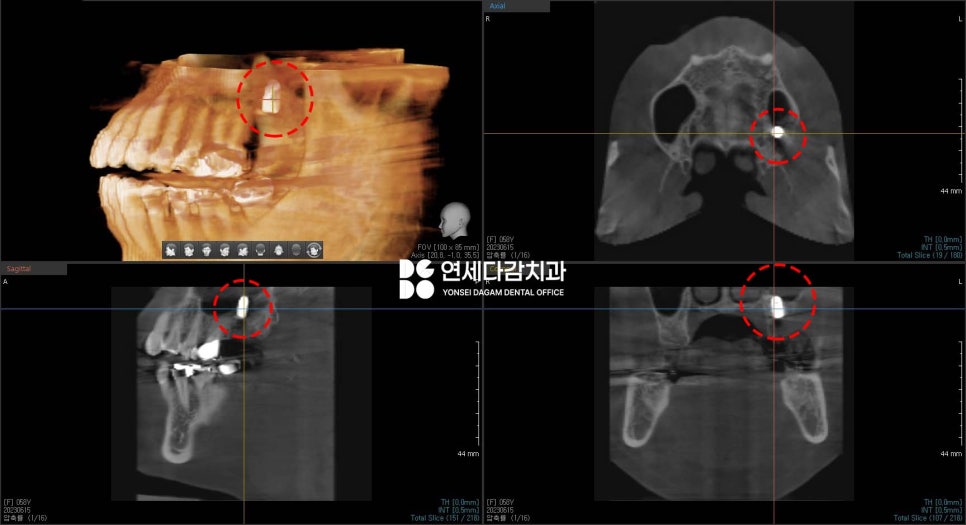

송파역 치과 에서

CT 촬영을 통해 정확한 위치를

분석하는 과정에서,

사랑니의 일부 부분이 상악동이라는

구조물과 접촉해 있는 것을

알 수 있었습니다.

상악동은 얼굴의 광대뼈와

코 사이에 위치한 공기로 채워진

빈 공간으로, 코와 연결되어 있는 구조물로,

만약 이 구조물이

천공된다면 여러 가지 합병증이

생길 수 있습니다.

이러한 이 구조물과 접촉되어 있는

사랑니를 뺀다면...

천공될 위험이 있는

상황이었습니다.